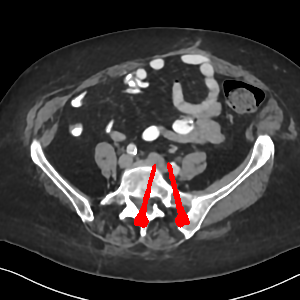

Effect of metal mask projection (SE0-Net vs SE-Net). From Table 1, we can observe the use of instead of improves the performance for at least 4.1 dB in PNSR and reduces MSE from 0.95219 to 0.00074 for all metal sizes. The groups with large metal implants benefit more than groups with small metal implants. As shown in Fig. 4, the artifacts in metal trace of SE0-Net are over-removed or under-removed, which introduces bright and dark bands in the reconstructed CT image. With the help of , SE-Net can suppress the artifacts even when the metallic implants are large and the surrogate data are more consistent with the correct data outside the metal trace.

Effect of sinogram padding (SE-Net vs SEp-Net). Sinogram padding mainly improves the performance in the group with the largest metal objects, with a PSNR gain of 0.15 dB and an MSE reduction of 0.00048. As shown in Fig. 4, the model with sinogram padding restores finer details of soft tissue between large metallic objects because more correct information is retained by periodic padding than zero-padding.

Effect of learning with (SEp-IE-Net vs Ours). When is jointly restored with the corrupted , the sinogram correction performance is affected with an increment of 0.00033 in MSE and of 0.7 dB in PSNR. More details of soft tissue around metal are retained and the image becomes sharper, as shown in Fig. 4.